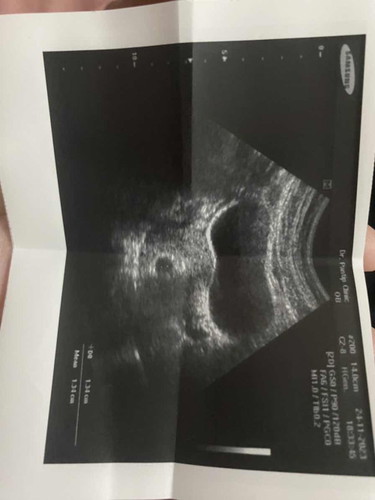

ท้อง6สัปดาห์แล้วแบบนี้จะมีน้องไหมคะ

วงกลมข้างล่างค่ะเป็นถุงตั้งครรภ์ หมอให้ดูแค่นี้เลย แบบนี้จะมีโอกาสท้องลมมั้ยคะ กลุ้มมาก

รออีกสองสัปดาห์ รอฟังเสียงหัวใจค่ะ